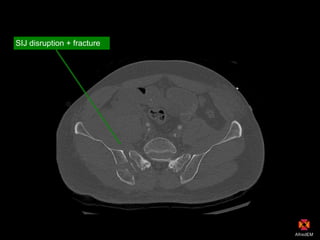

Pelvic haematoma

SIJ disruption + fracture

CT scan

Extraperitoneal

bladder rupture

with contrast leak